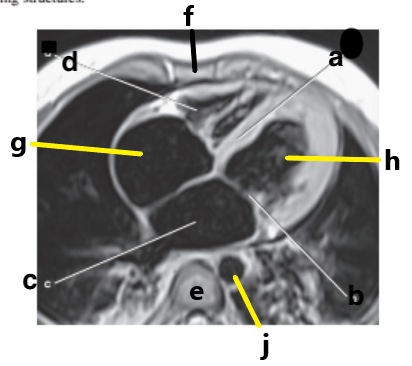

Which letter is pointing to the posterior cruciate ligament?

e

Which letter is pointing to the patellar ligament?

b

Which letter is pointing to the anterior cruciate ligament?

c